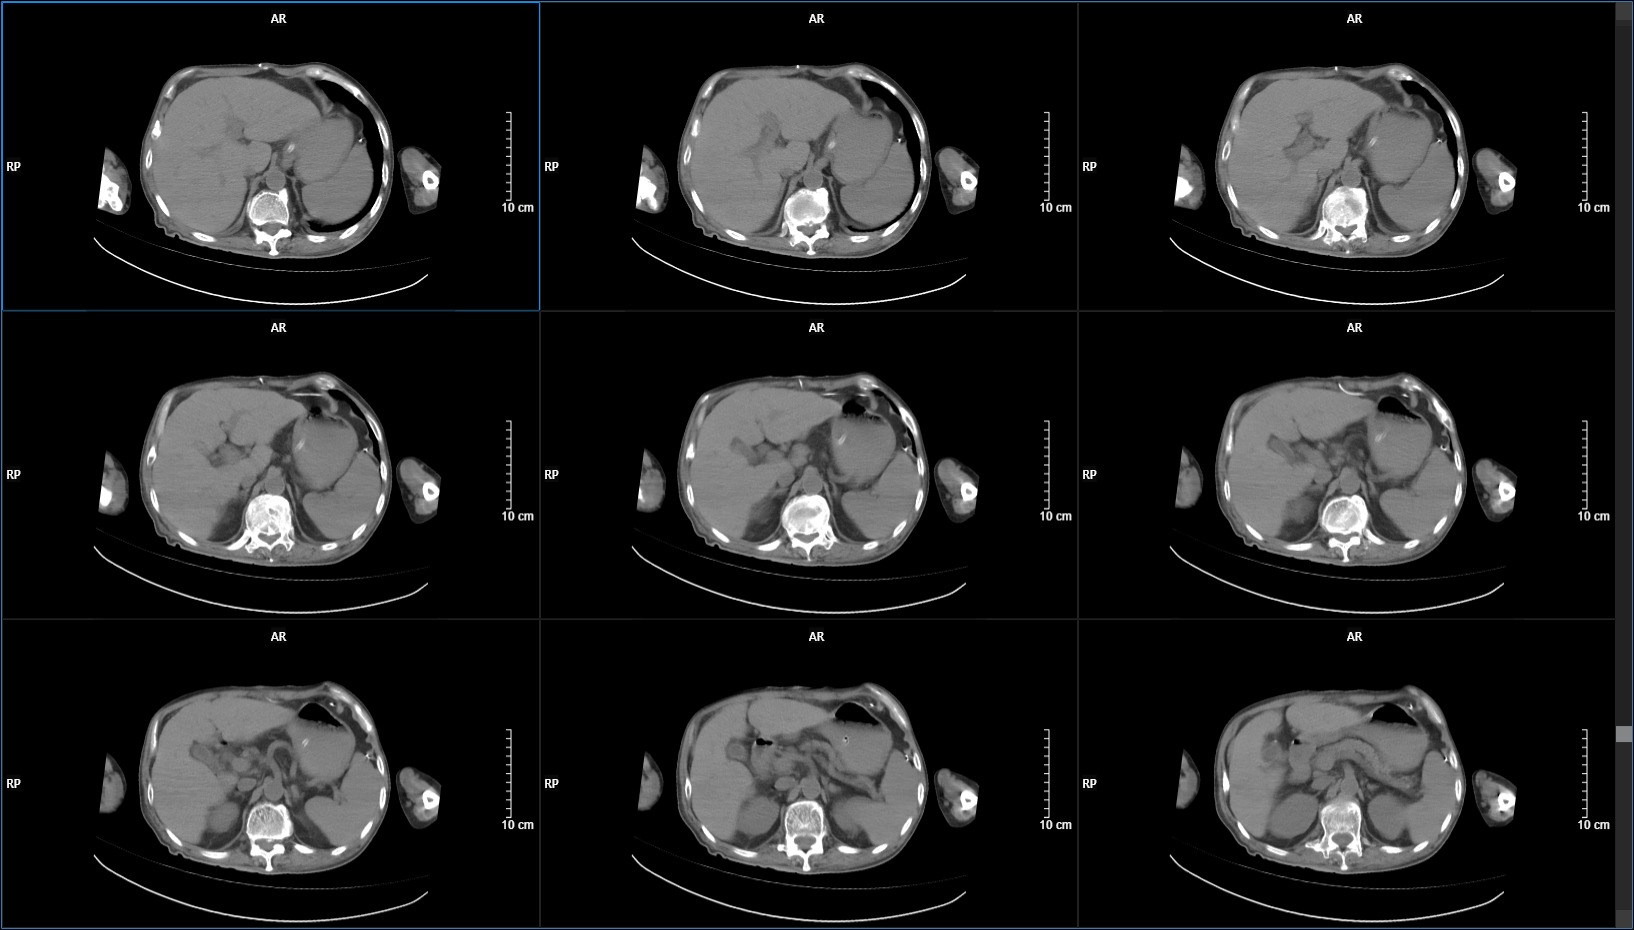

1周后,患者大便呈墨绿色稀便,腹腔出现积液,颅脑复查无变化。伴高热,血感染指标升高明显,但腰穿脑脊液结果正常,腹腔引流液化验结果也无异常。应用万古霉素、利奈唑胺等均效果差。意识也逐渐变差。

考虑腹腔分流管相关导致腹腔感染(仍然疑惑,各项检查数据均正常,无菌性炎症?网膜不吸收原因?),给予腹腔引流+拔除腹腔分流管,未在出现腹腔积液。但意识也回到入院时水平,肺部感染等并发症也逐渐出现。